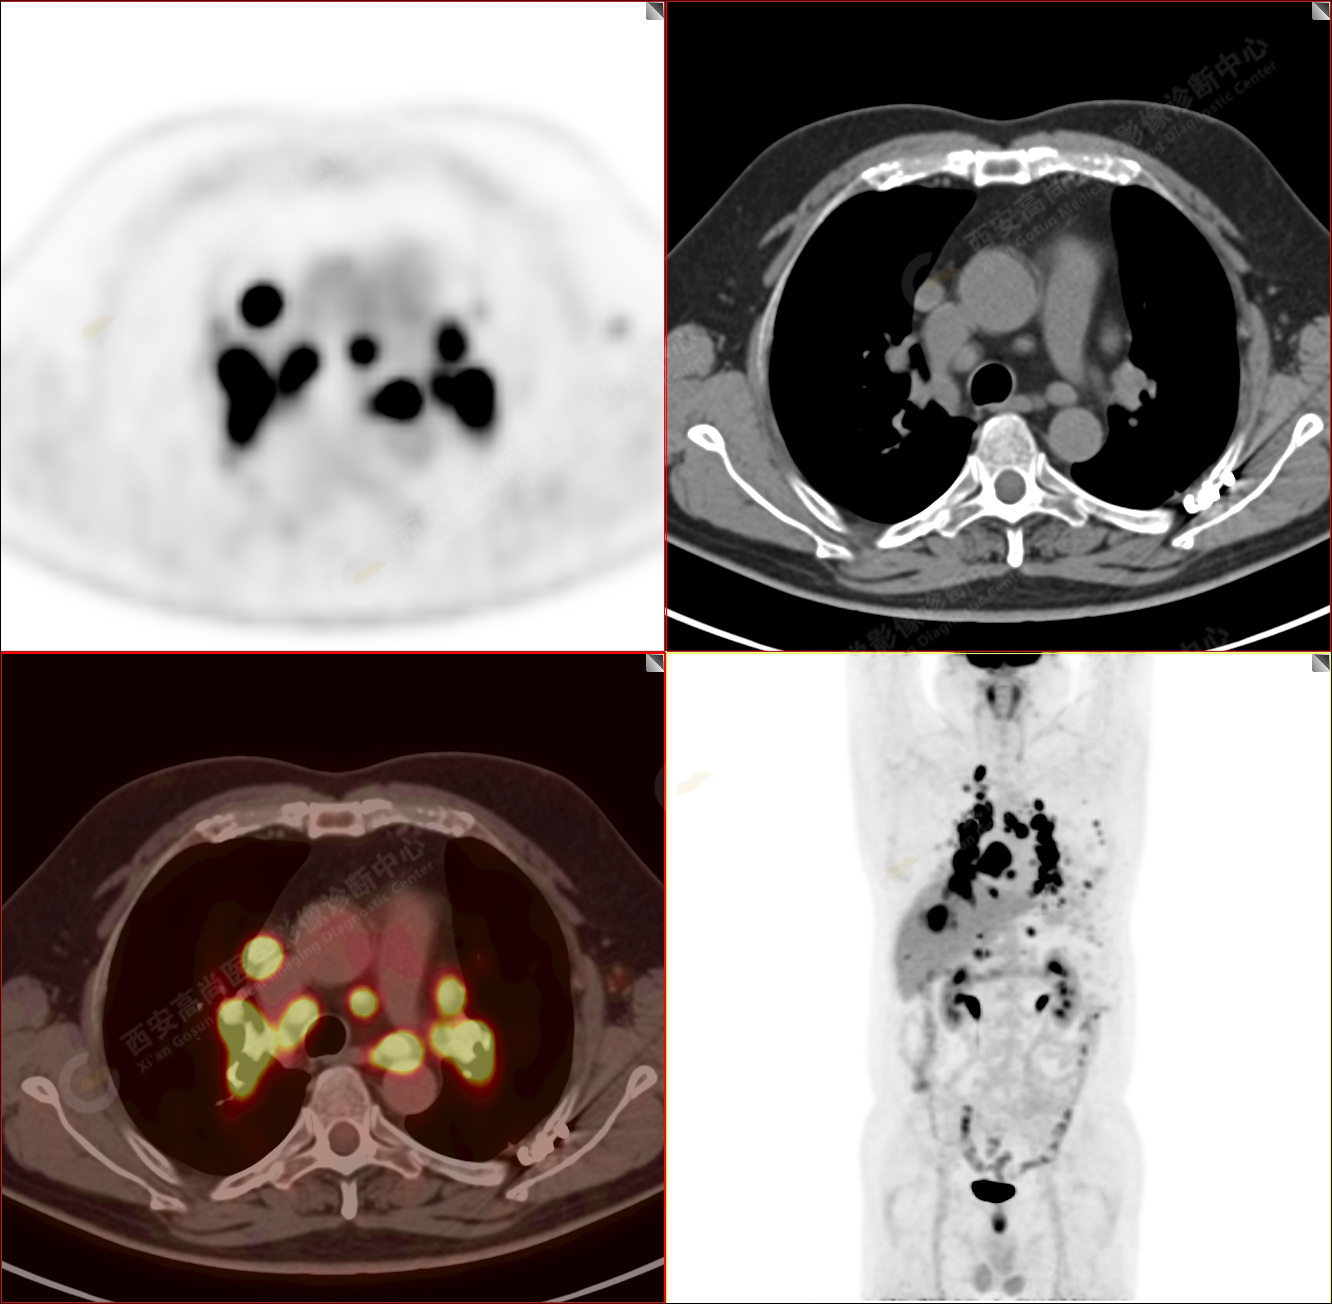

男性,53歲,頭暈半月入院,CT發(fā)現(xiàn)肺內(nèi)腫塊,雙肺多發(fā)大小不等實(shí)性及粟粒樣結(jié)節(jié),雙肺門(mén)及縱隔多發(fā)腫大淋巴結(jié)。病程中無(wú)發(fā)熱、胸悶氣及胸部不適。既往:左側(cè)肋骨外傷史。

PET-MR圖像